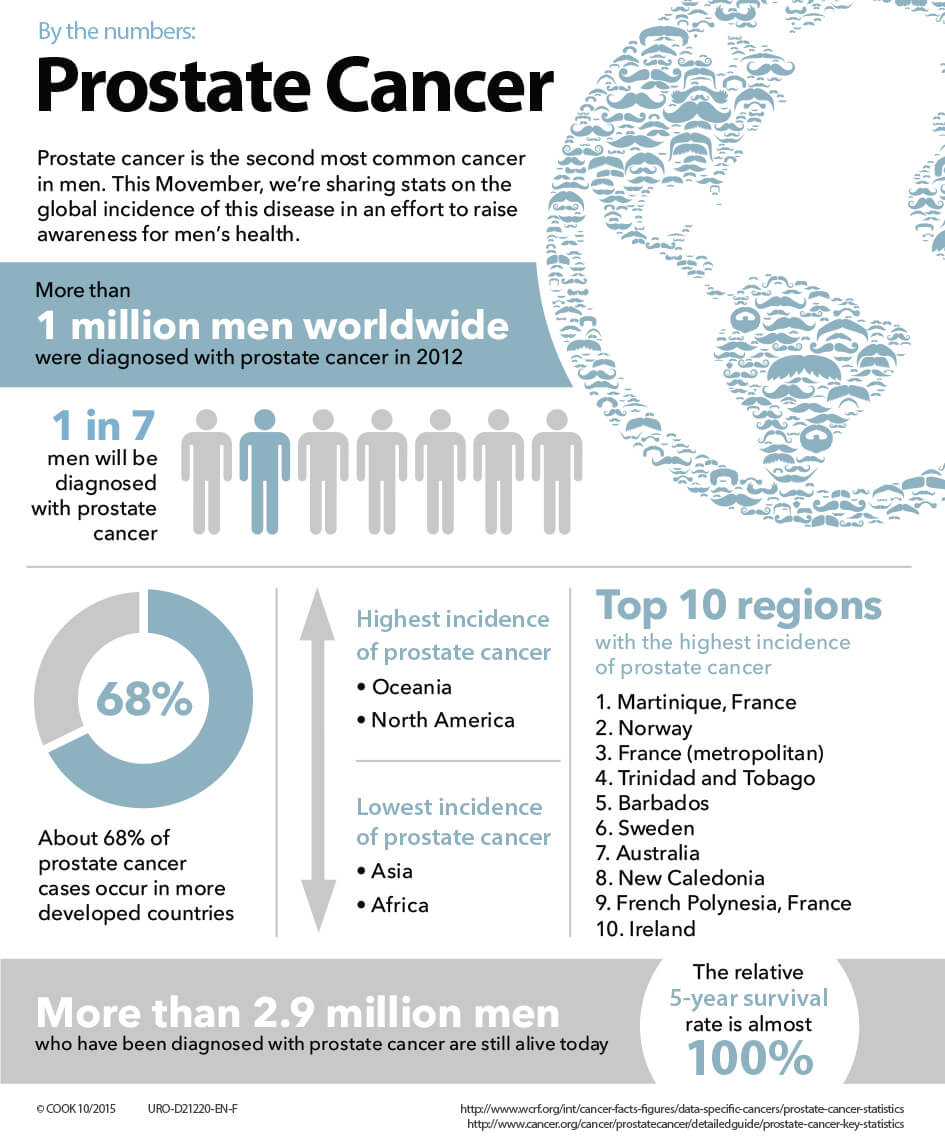

By the numbers: Prostate cancer | Urology

Prostate Cancer the Most Common in Men, September is Prostate Awareness …

Prostate Cancer Facts – Prostate Cancer Research